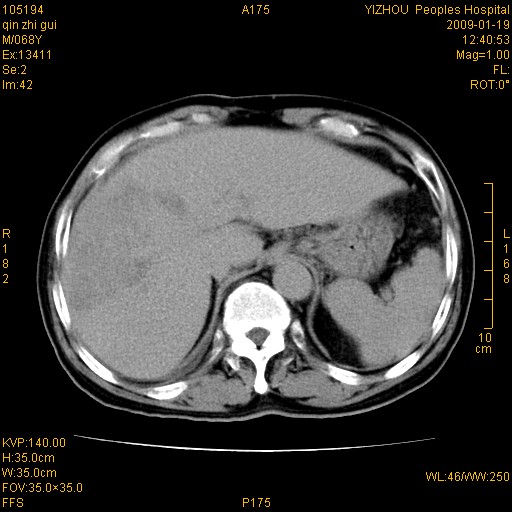

以下是引用随光逐影在2009-1-21 16:11:00的发言:[br]1)考虑肝右叶肝癌并肝静脉及门静脉瘤栓形成。2)肝硬化,少量腹水。3)胆囊炎。4)右侧少量胸腔积液。

病灶外缘凹凸不平,平扫低密度,增强动脉期有强化,门脉早显,静脉期及延期呈延迟强化,结合病史考虑右肝前叶巨块型肝癌可能性大,强化表现不除外胆管细胞癌